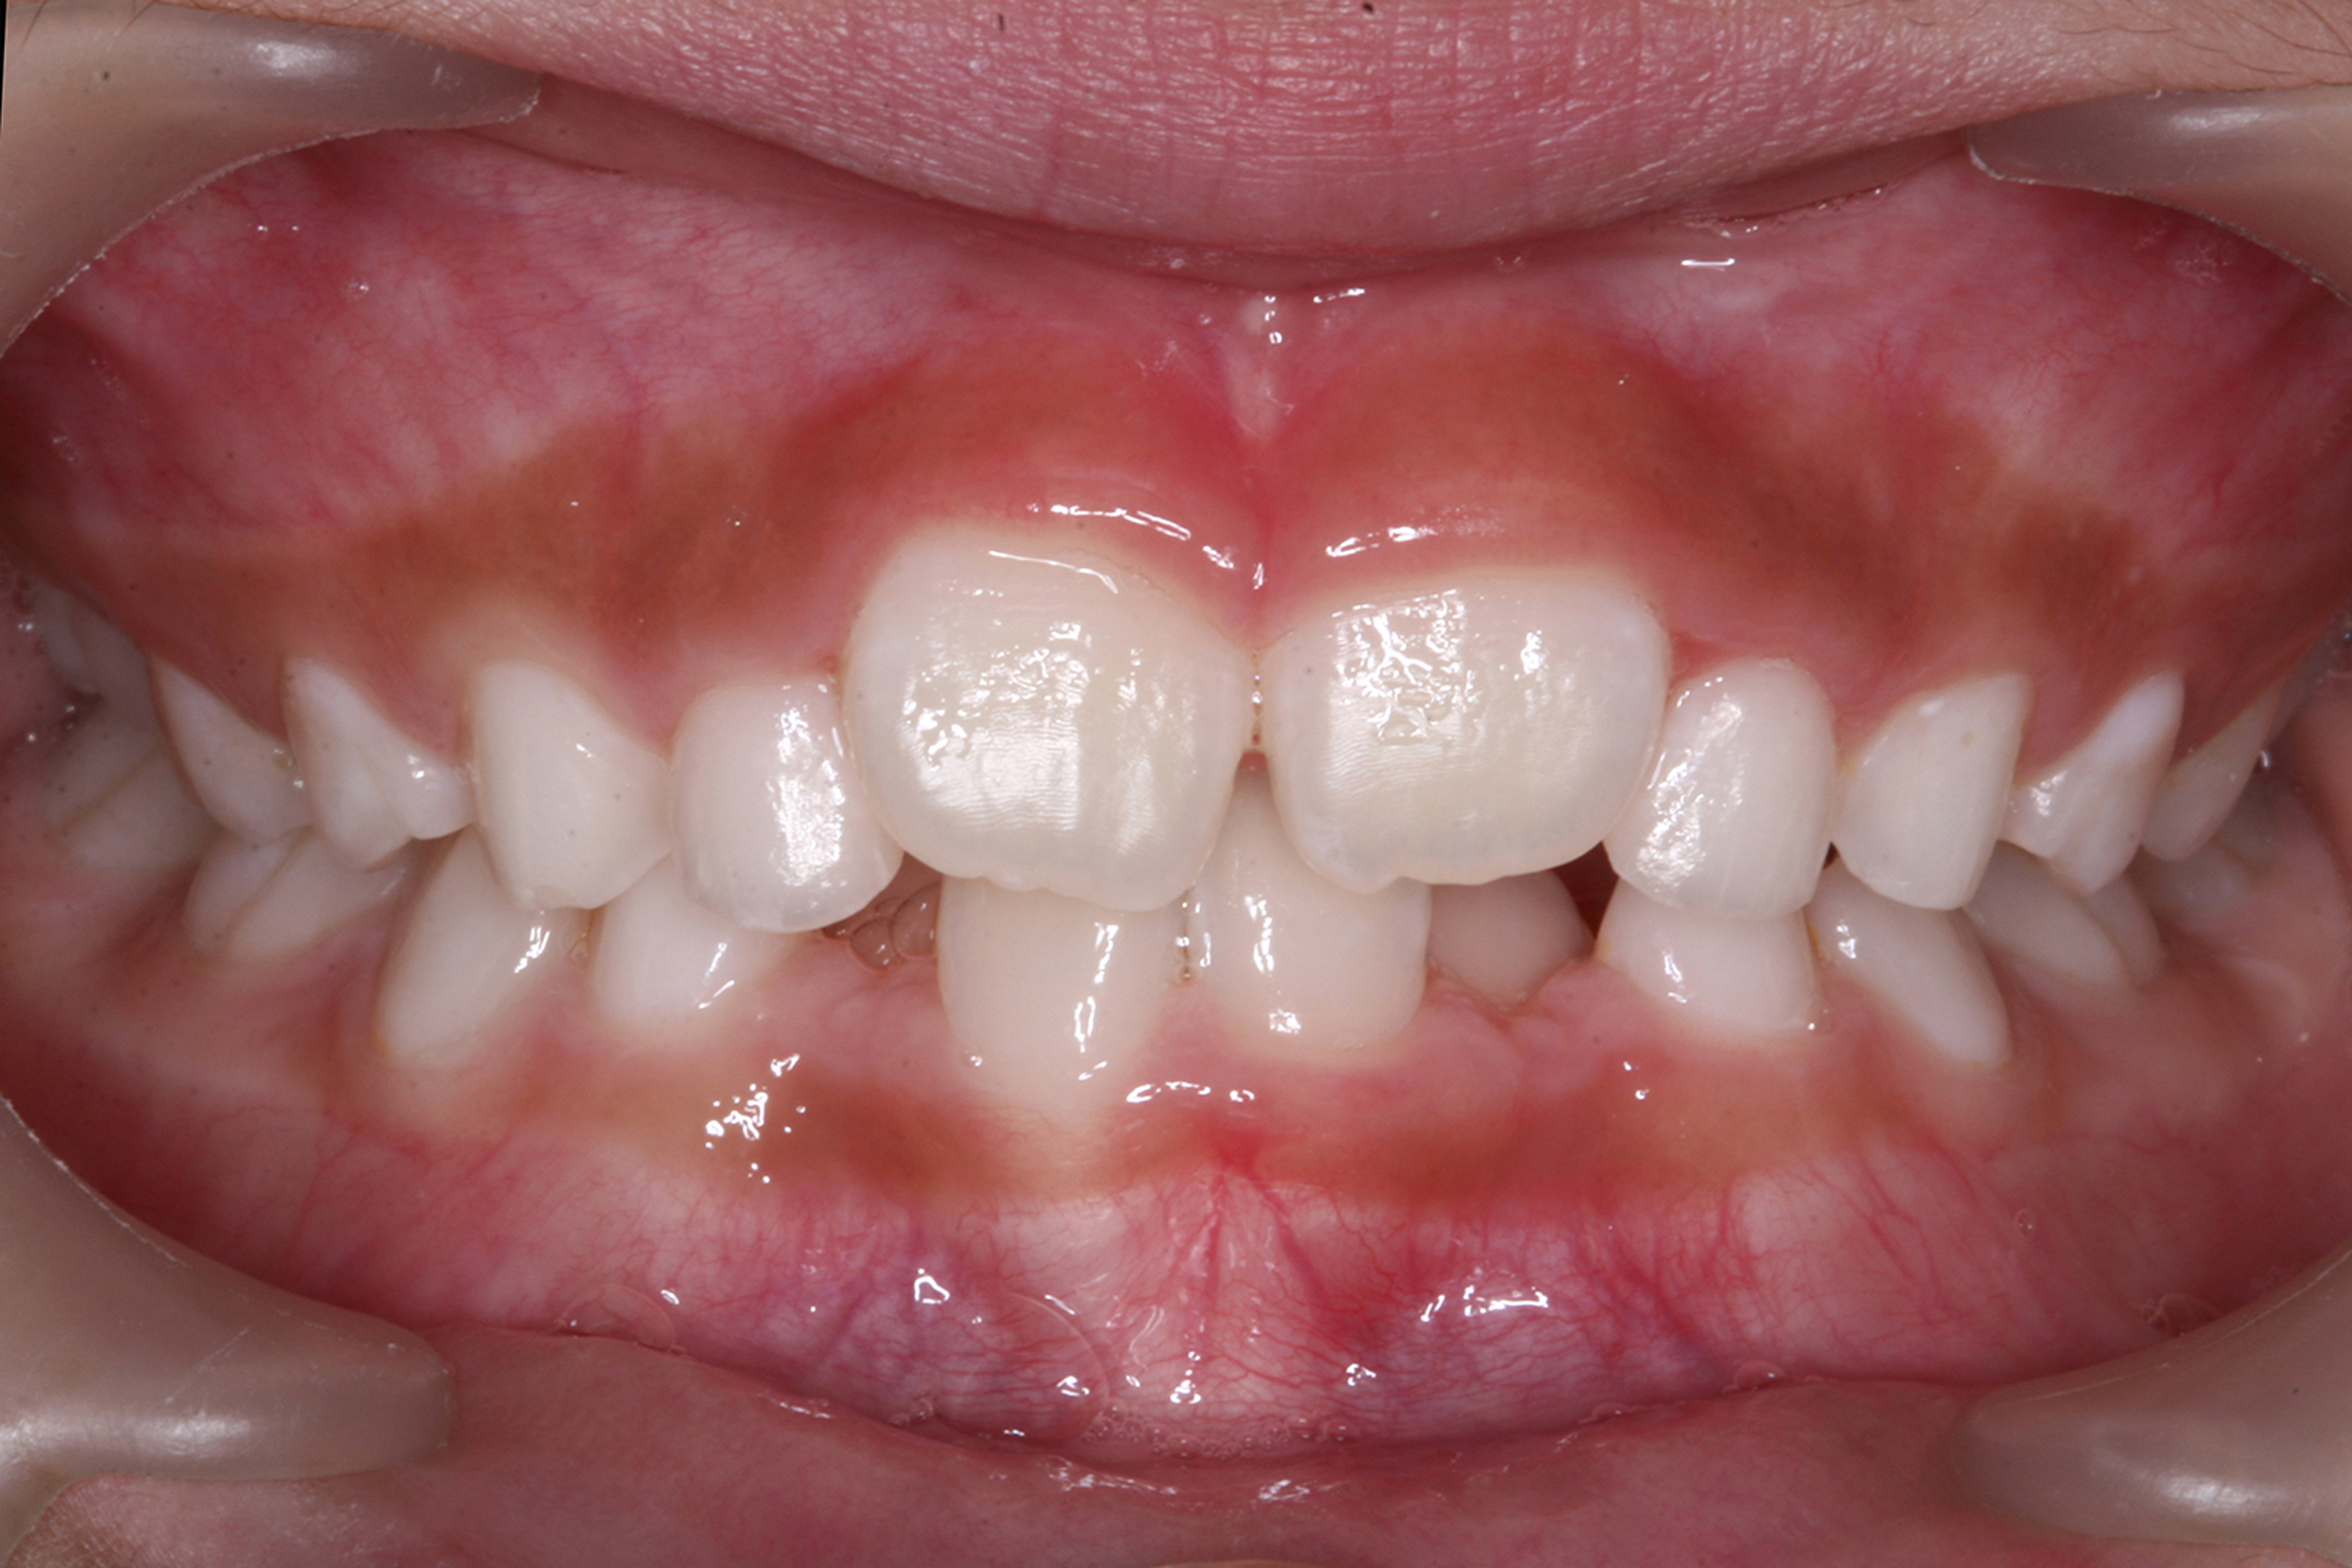

日本で行われている拡大床治療にも色々な方法がありますが当院での特長は最初に永久歯に生え替わる上下4本の前歯を奥歯の生え替わりが始まる前までに顎を拡大してきれいに並べることです。そのため拡大床治療の期間は小学校1年生頃から4、5年生頃までの間に限定しており、それまでに目的が達成できない場合には別の治療法に移行します。またゆっくりスペースを獲得するようにしているのも特長で2週間に1回ネジを回すようにしています。一般的には1週間にⅠ回ないし2回ネジを回すことが多いようです。ゆっくり進めるので一日の装着時間はお家にいるときと寝ている間だけにしています。学校や自宅以外での装着はせずゆっくり拡大していくので治療期間が長くなりますが後戻りは少なく確実になります。治療開始時期が大切ですので時期を逸した場合には拡大床治療は行いません。一般的に拡大床治療の評判が悪いのは開始時期が遅く、いつまでも治療を長引かせ治らないことによるものが多いようです。 拡大床治療はスペースを作って永久歯がならぶスペースを作ることが目標ですので細かい歯の向きや角度まで整えられないこともあります。そんな場合には別の矯正治療が必要になります。

拡大床治療で顎のスペースを拡げられるのは11歳くらいまでです。そのため個人差はありますが遅くても小学校2年生までに始めなければなりません。下の前歯が生え替わりはじめた頃から下の前歯が4本、上の前歯が2本生え替わる頃までが始め時です。すでに上下4本とも生え替わってしまった場合にはすでに遅いことが多くあります。

拡大床治療ではすべての歯がきれいに並ぶように顎の成長を促すことが目的ですので細かい歯の位置や角度までは調整できません。また歯が大き過ぎる場合には口の中で歯が目立ちすぎることになる場合もあります。日本人を含めたアジア系の骨格には特長があり、ヨーロッパ系の顔立ちとは基本的に違っていますが上下の歯を抜いたりすることでそれに近づけることもできます。矯正専門の歯科ではそのような目標を立てて治療を行うことが多く、そのために4本の永久歯を抜歯することもあります。拡大床治療では歯を抜かずすべての自分の歯でしっかり噛めることを目標にしていますので口元のきれいさを目的にする治療とは異なります。歯を抜いて口元をきれいにするのは大人になってもできる治療ですので、親としては先ずはお子さんのすべての歯を使ってきれいに歯をならべることを優先すべきで、あとで本人が口元が気になるというのであれば本人の意志で歯を抜いて矯正治療を行うべきであるというのが当院の考えです。